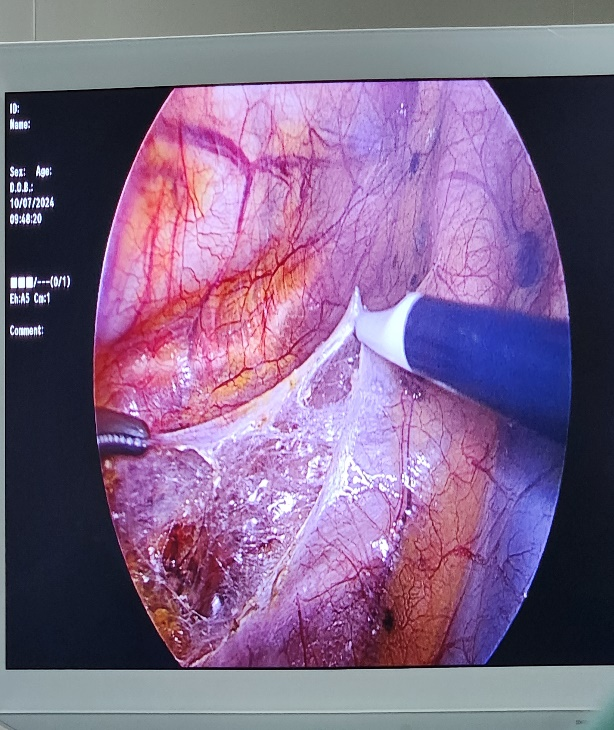

近日,宣汉县第二人民医院胸外科团队顺利完成了一例“胸腹腔镜联合下食管癌切除胃代食管左颈部吻合术(Mckeown)”。胸腹腔镜联合下食管癌切除术是一种微创、安全、有效的食管癌手术,在胸腹腔镜联合下胸腹部仅各需4个0.5-1.2厘米小切口即可完成该手术。此项技术的开展填补了我院食管癌治疗的空白,标志着医院在胸外科微创技术领域实现又一新突破,让患者实现了手术创伤小、花费少、出院早。

该患者为70岁男性,因“进食梗阻感1+月”就诊,我院胃镜检查提示:距门齿约27cm-31cm段4点-11点位见溃疡型新生物致管腔狭窄,病检提示:鳞状细胞癌,当得知要手术时患者及亲属有许多的担忧。对于患者的担忧,彭浪副主任带领胸外科团队在术前常规进行了科室讨论,为患者制定个体化的最优治疗方案。考虑到患者年龄偏大,为减少手术对患者的创伤,提高手术效果,经过讨论,决定采用胸腹腔镜联合下食管癌切除胃代食管左颈部吻合术(Mckeown)。该术式为目前治疗食管癌最微创且有效的术式,在向患者及其家属说明微创的特点和优势,征得同意后,由彭浪副主任主刀,手术按计划顺利进行,术中通过胸腹部仅各需4个0.5-1.2厘米小切口及左颈部、腹部各4cm小切口,在胸腹腔镜联合下为患者成功切除食管癌,并重建消化道。术后术区疼痛轻微,术后第四天进食流质饮食,术后第八天顺利出院。病情恢复良好,患者及家属均表示非常满意。